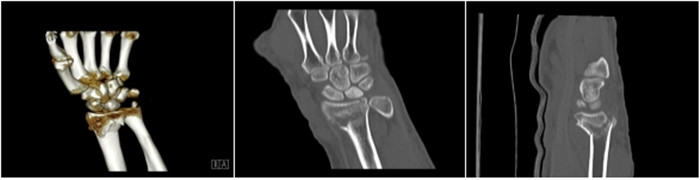

明峰CT搭載了領(lǐng)先的硬件技術(shù)平臺(tái)及系統(tǒng),強(qiáng)大的掃描能力可滿(mǎn)足臨床的各種要求,呈現(xiàn)更極致的細(xì)節(jié),為各臨床科室提供高品質(zhì)的圖像。薄層掃描,消除部分容積效應(yīng),提高各向同性。配合高分辨率算法,有助于細(xì)微結(jié)構(gòu)和形態(tài)學(xué)顯示。